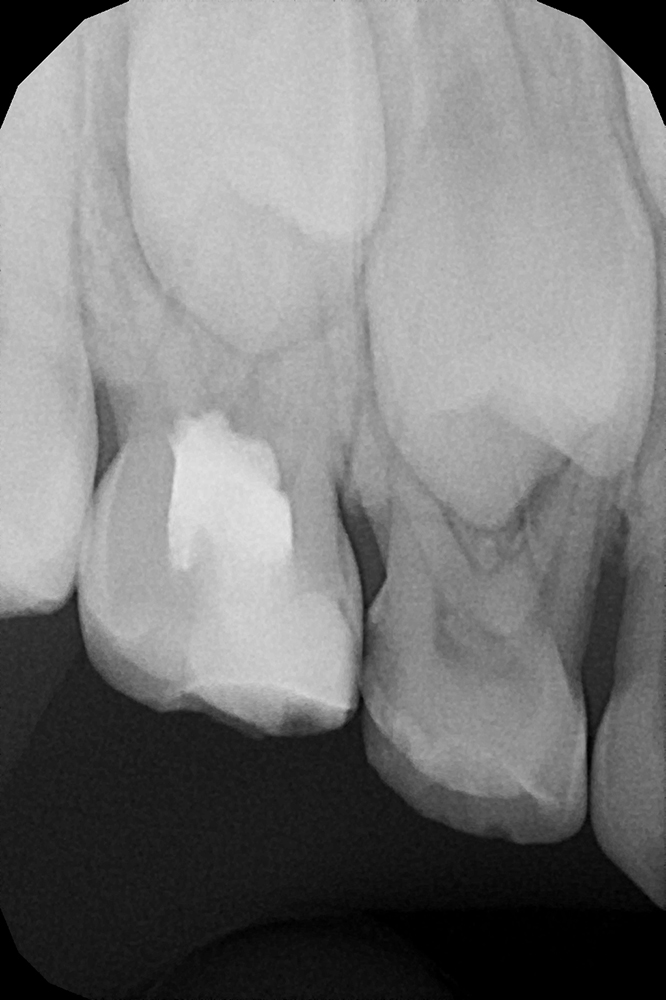

Диагностика и лечение скрытого кариеса на постоянном зубе у семилетнего ребёнка